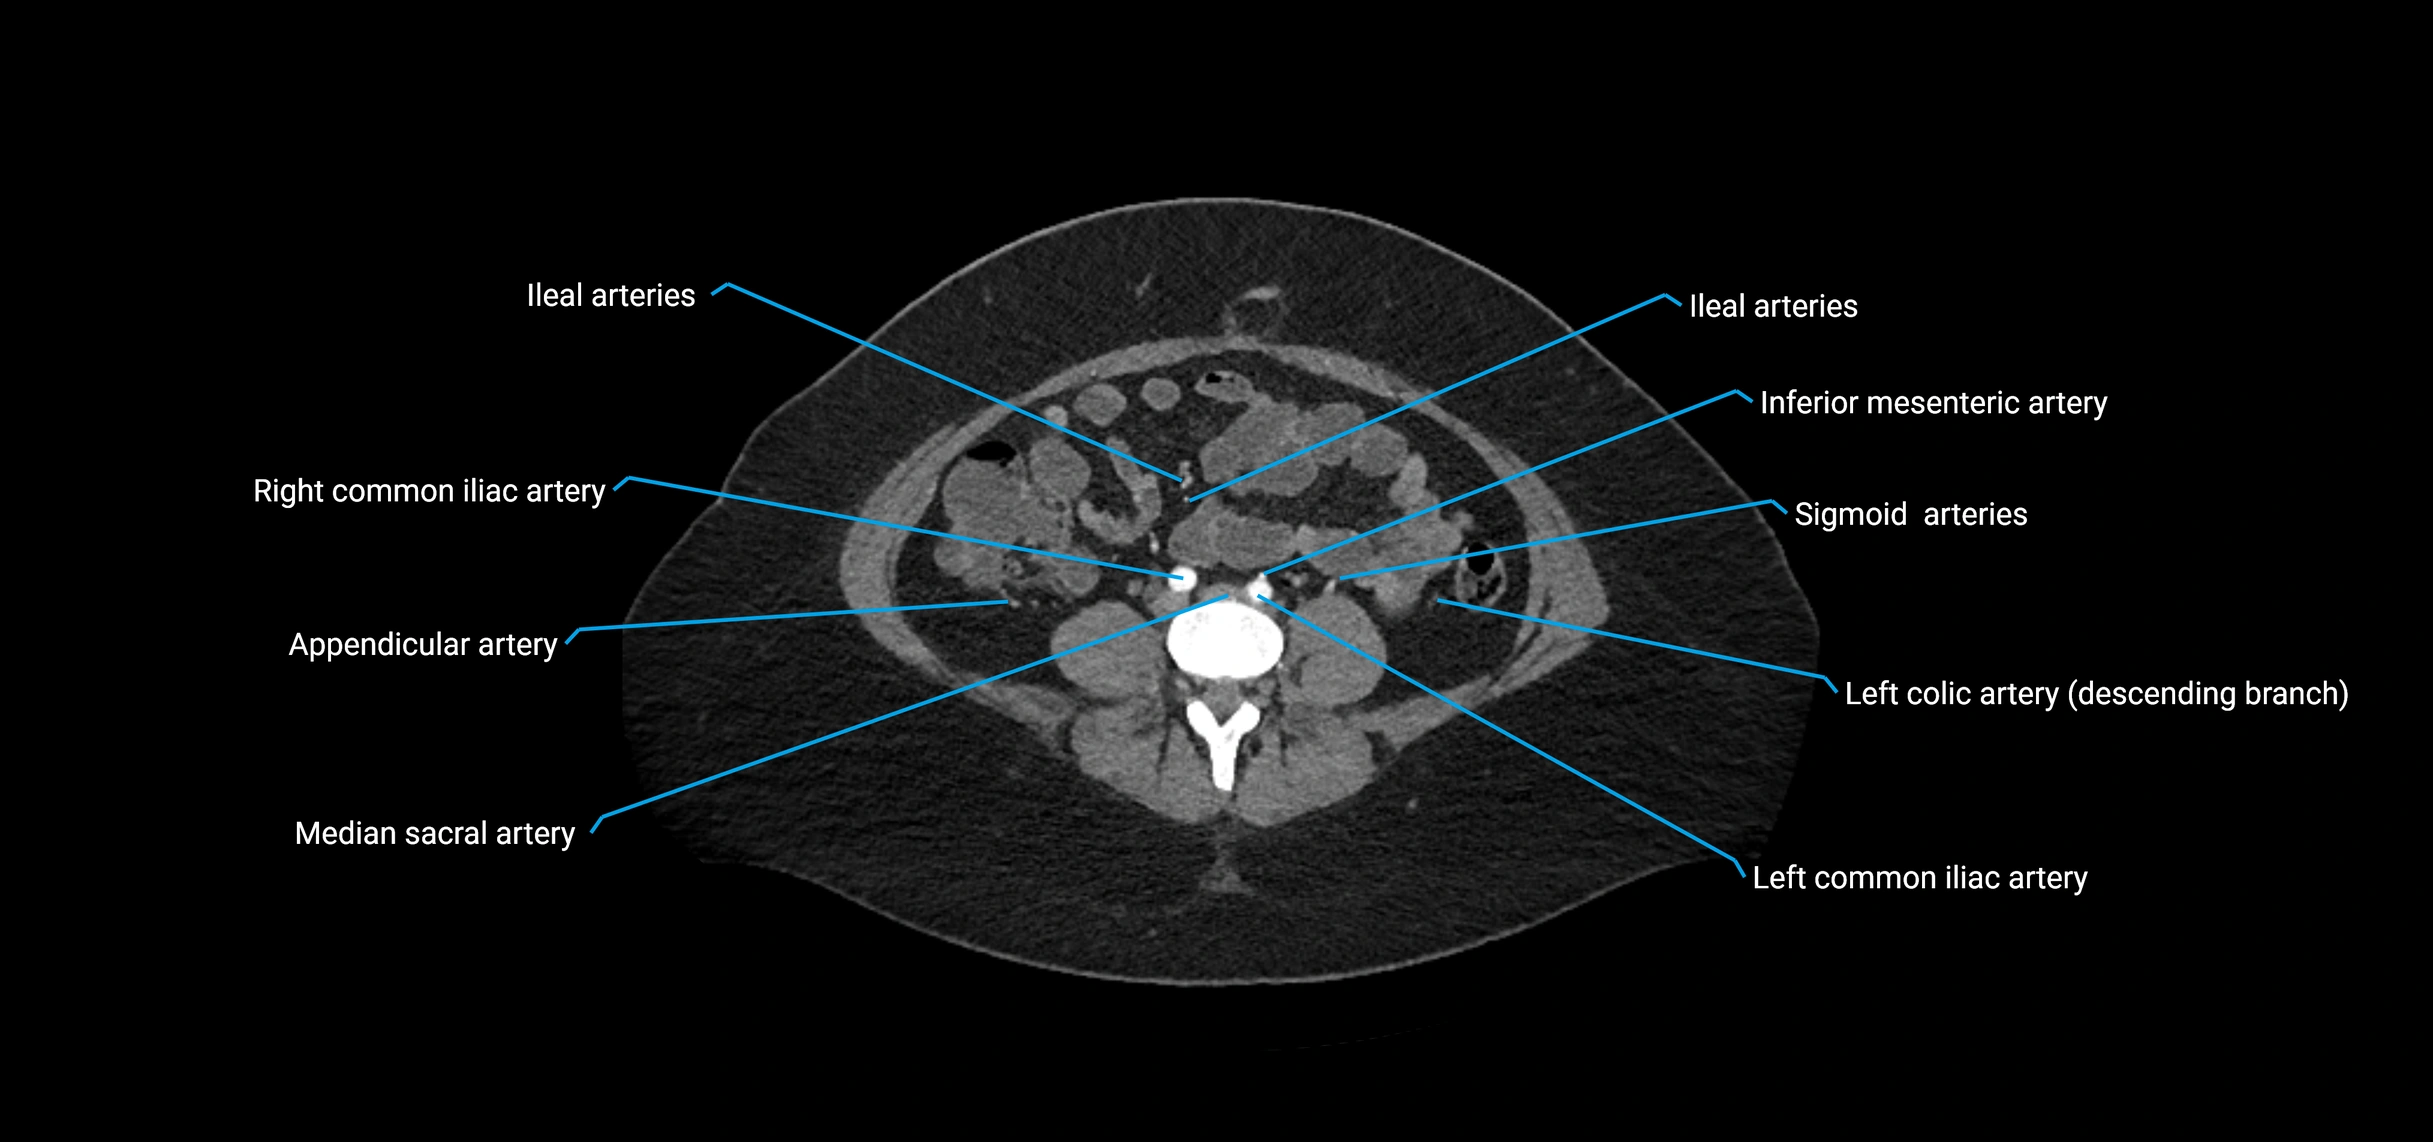

Contrast-enhanced CT (CTA):

• Gold standard for abdominal aortic imaging

• Provides excellent detail of lumen, wall, aneurysm, thrombus, and branch vessels

• Multiplanar and 3D reconstructions help in aneurysm measurement, stent graft planning, and dissection evaluation

• Detects acute rupture, traumatic injury, or occlusion with high sensitivity